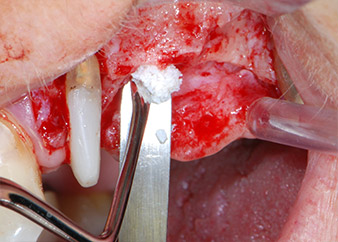

Prior to implant placement, infected tissue was removed from the alveolar bone in the implant site and around the abutment teeth with an insert originally designed for bone shaping and collecting bone chips (Piezomed, insert B5) (Figs. 6 and 7).

Prior to implant placement, and following verification of an intact Schneiderian membrane (Fig. 9), the internal sinus floor was augmented at both implant sites by means of xenogeneic bone substitute material (Bio-Oss, Geistlich Biomaterials) (Fig. 10).

Bone deficiencies around the implants, at the mesial aspect of tooth 27 and around the buccal root of tooth 24, were filled with xenogeneic bone substitute particles and covered with an absorbable collagen membrane (Bio-Gide, Geistlich Biomaterials) for GBR augmentation (Figs. 13 and 14).

Xenogeneic bone substitute material

Fig. 13: Xenogeneic bone substitute material was used to fill the remaining osseous defects …

absorbable collagen membrane

Fig. 14: ... which was then covered with an absorbable collagen membrane. The grayish-pink structure between the elevators at the top margin of the picture represents interproximal papillary tissue.